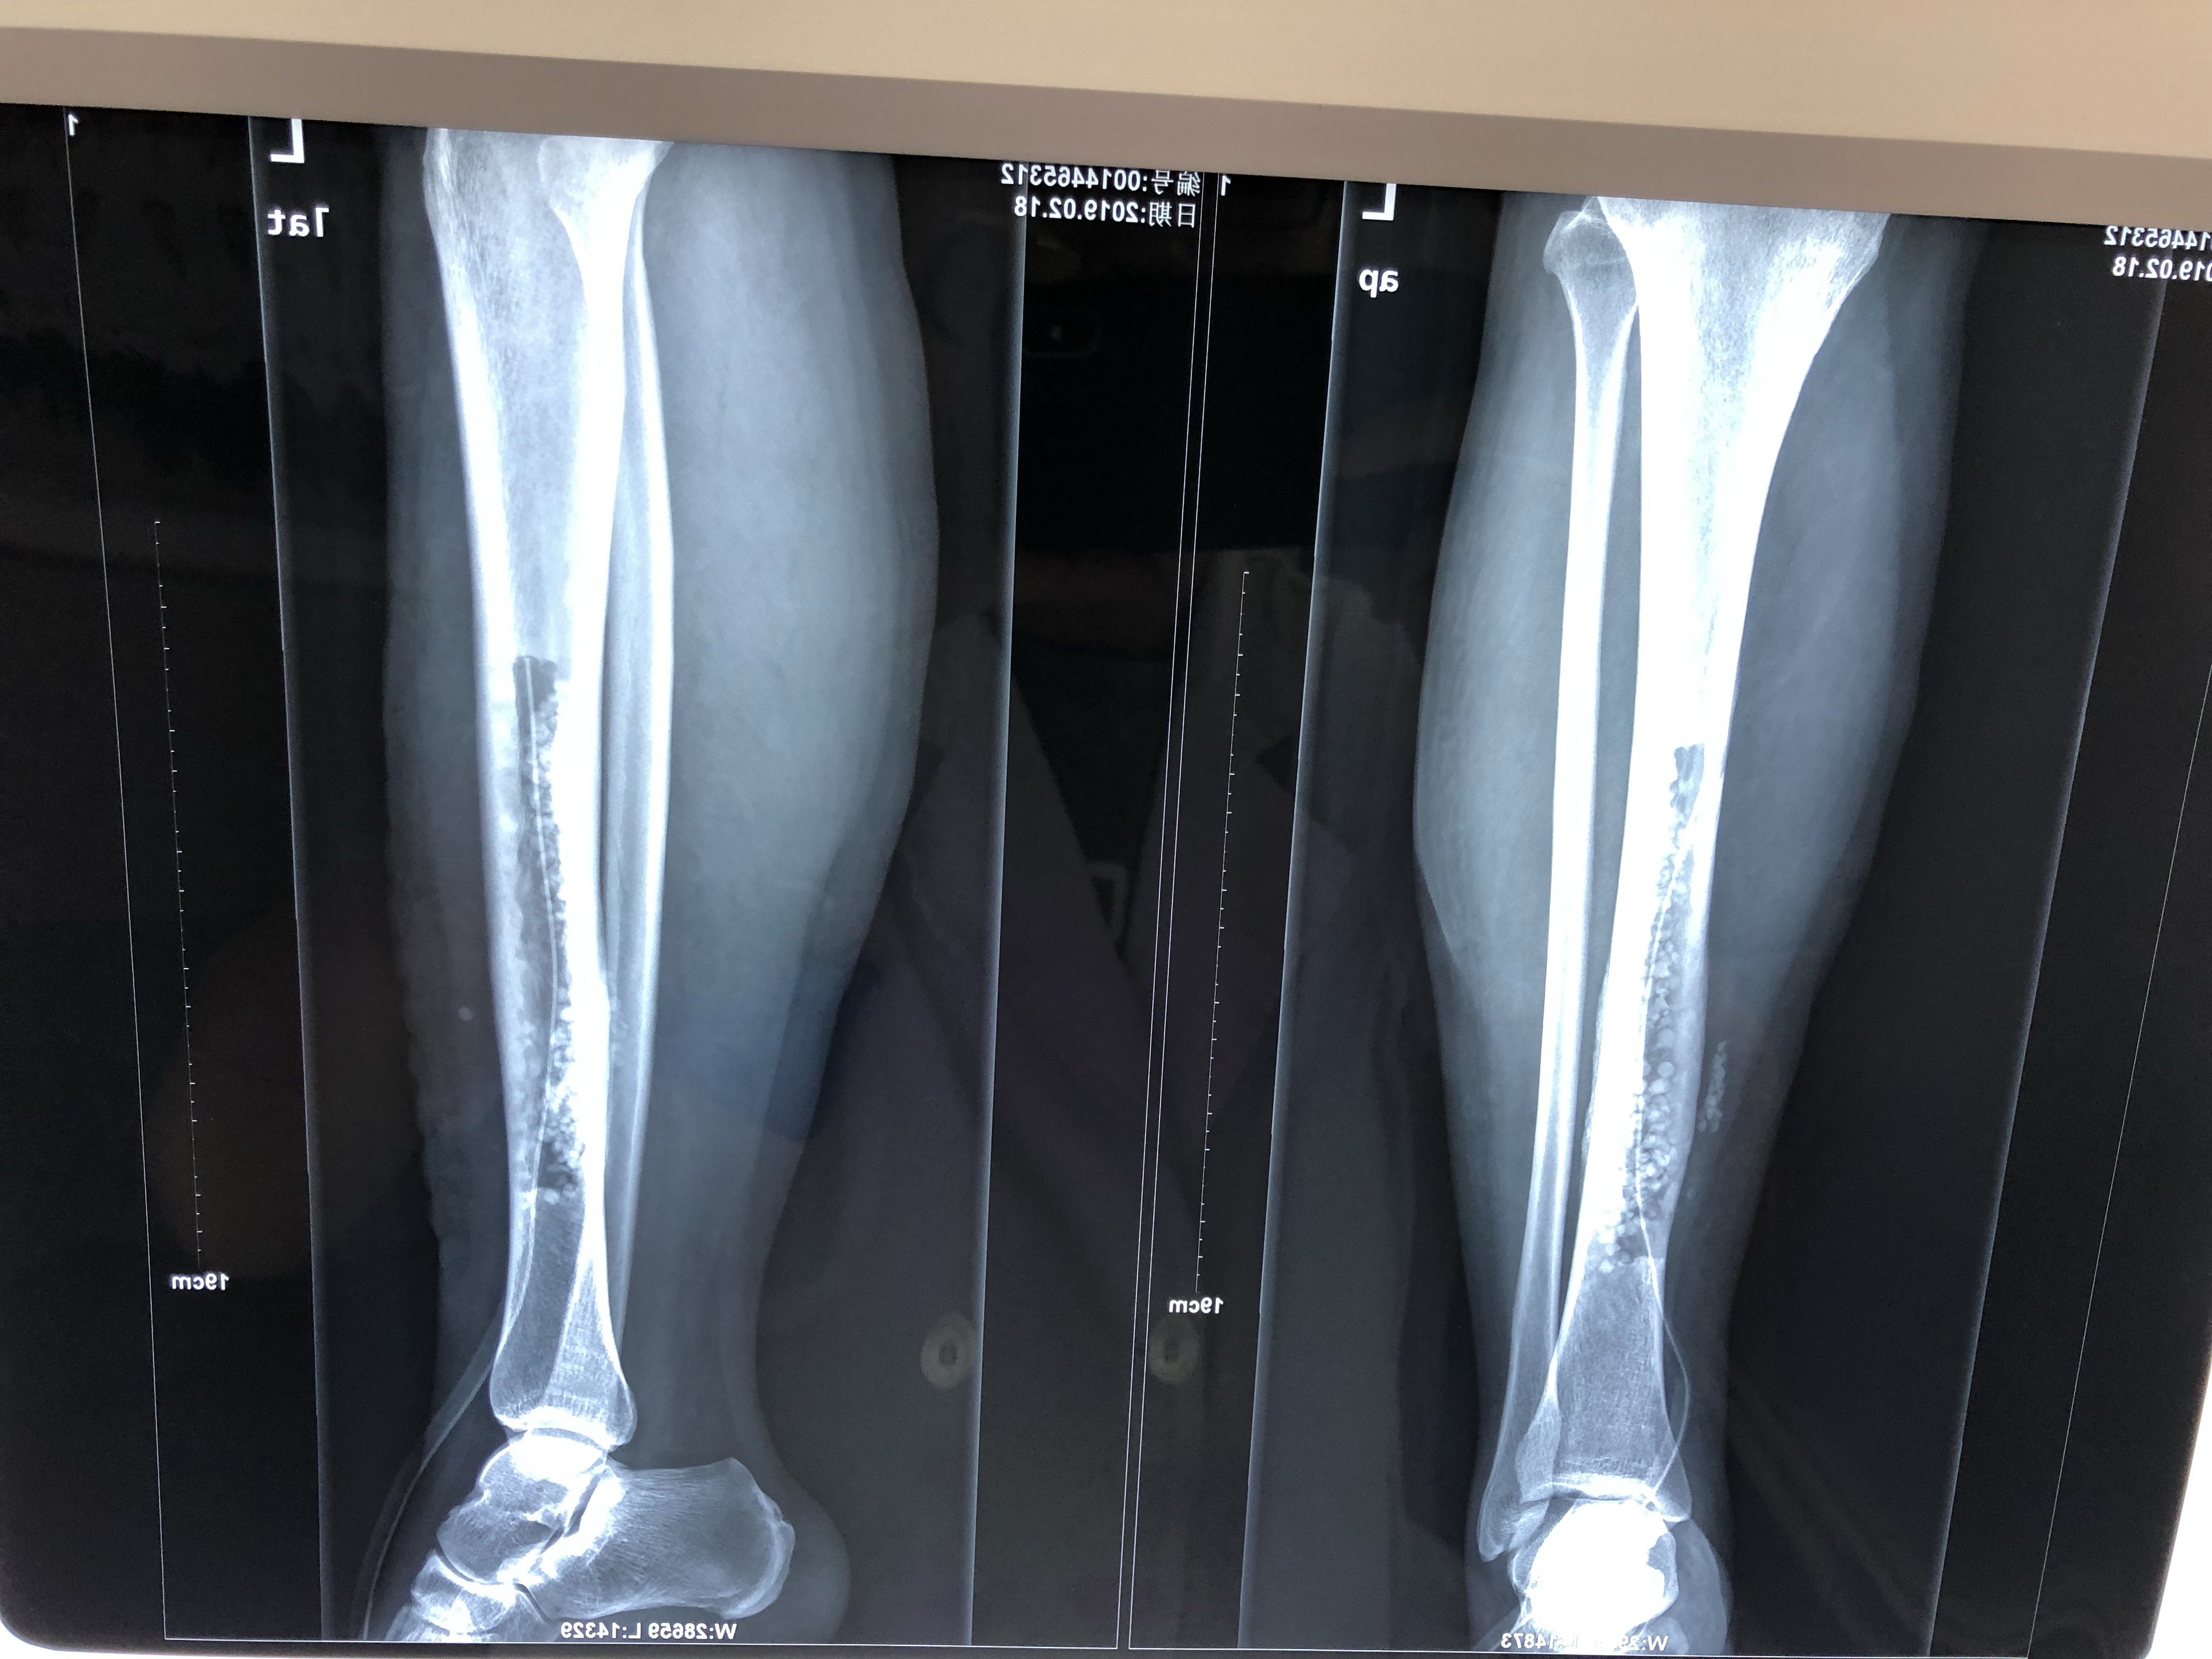

年轻人x线腿显示胫骨骨髓炎照片

左胫骨慢性骨髓炎

慢性骨髓炎伴骨外漏

这一例胫骨慢性骨髓炎大家有啥好建议

胫骨慢性骨髓炎